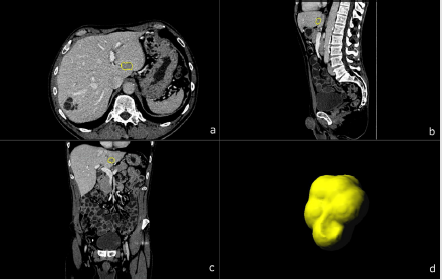

Figure 2: A 69-year-old male patient with biopsy confirmed CCC. Multiplanar image annotation in axial

a) sagittal

b) coronal

c) 3D reformats.

d) of the CCC lesion. Assessing figure 1 (HCC) and figure 2 (CCC) side by side highlights the difficulty of visual differentiation in a single (portal venous) phase.

One central aspect of this retrospective evaluation of textural features consisted of the possibility to overcome the limitations related to one-phase portal-venous CT-protocols in the differentiation of HCC and CCC (refer to Figure 1 and Figure 2) whilst avoiding unnecessary radiation exposure due to multi-phase protocols required for accurately classifying their enhancement patterns. Our data shows that four of the thirty-five calculated radiomics features derived from the portal-venous enhancement phase proved significant for differentiation of HCC from CCC on a standalone basis. Whereas three of them represent differences in tumor tissue attenuation (1st order Mean, Median and Maximum) one is a measure of local tissue homogeneity (glcm Idmn). All of them yielded significantly higher absolute values for HCC compared to CCC. The use of combinations of features resulted in additional significances. Hence, the use of a combination of two textural features like 1st order Maximum and grey-level dependency matrix dependence non-uniformity or neighboring grey-tone difference matrix (ngtdm) contrast resulted in a slight increase in sensitivity, but also a slight decrease in specificity. The same was observed for the gray-level co-occurrence matrix (glcm) combined with the gray level run length matrix run entropy.